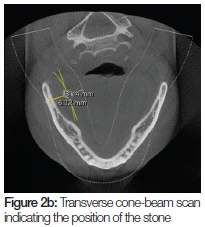

A cone-beam scan was undertaken in order to establish the size of the stone and its relative position with respect to the medial border of the mandible (Figure 2 A and B). The stone was found to measure 6.43mm in greatest diameter.